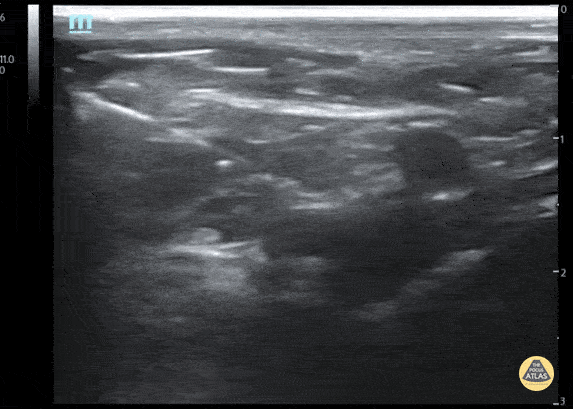

Fascia iliaca nerve block for 3yo M with left femur fracture Contributor: Julia Brant, MD, Children's Hospital Colorado, @pedipocus